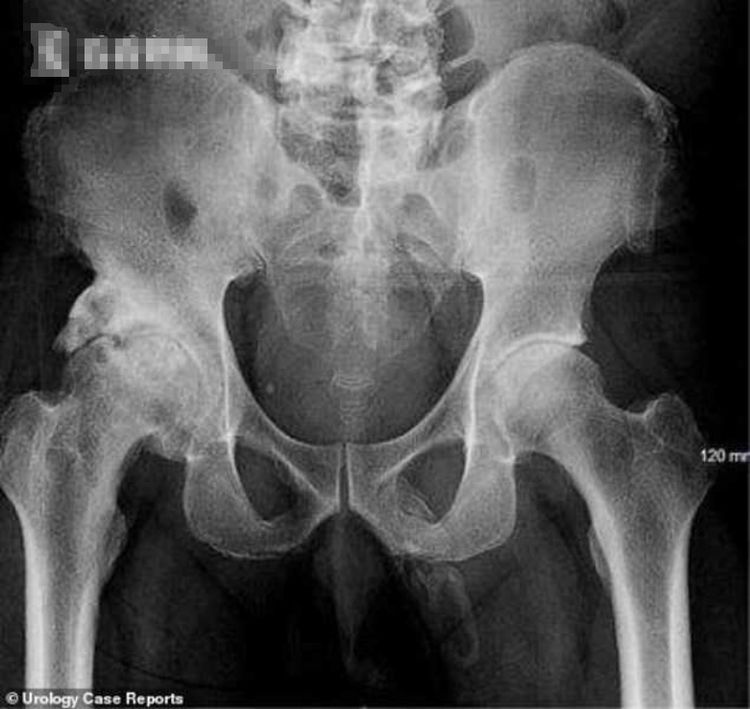

就在前段时间突尼斯某家医院又迎来了一位奇葩事情,十四岁小男孩有三天没有正常排尿了,下面很痛,医生就先让病人拍个片检查一下,当医生看到X光片的时候,医生都被眼前的一幕吓傻了,X光上面显示男孩的尿道里面有一根长达九厘米的缝衣针,据该男孩说当时只是为了好奇和得到快感才做出这样的事情。

在医生的帮助下,在小男孩的尿道5厘米处找到了那根9厘米的缝衣针的位置,然后对小男孩用了全身麻醉用镊子把针给取了出来,这次的手术非常的顺利,男孩在第二天就能出院了,然而医院方面却觉得这个小男孩可能有特殊性癖好才做出这样的事情。